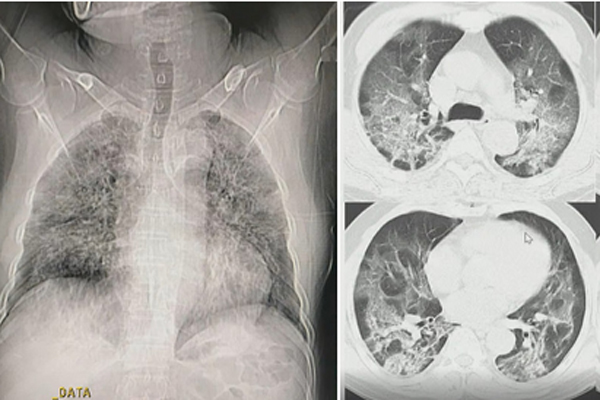

Trong đó, trường hợp nặng nhất là BN812. Hiện tại, chức năng phổi của người này đã tổn thương đến khoảng 70%. Ngay khi nhập viện, bệnh nhân đã ở trong tình trạng nặng, phải thở oxy và điều trị tại Khoa Cấp cứu. Tuy nhiên, bệnh nhân dần diễn tiến nặng hơn, có biểu hiện yếu cơ, mệt mỏi, suy hô hấp khi thở máy không xâm nhập. Người bệnh được chuyển lên Khoa Hồi sức tích cực đêm 12/8 và phải đặt ống thở máy.